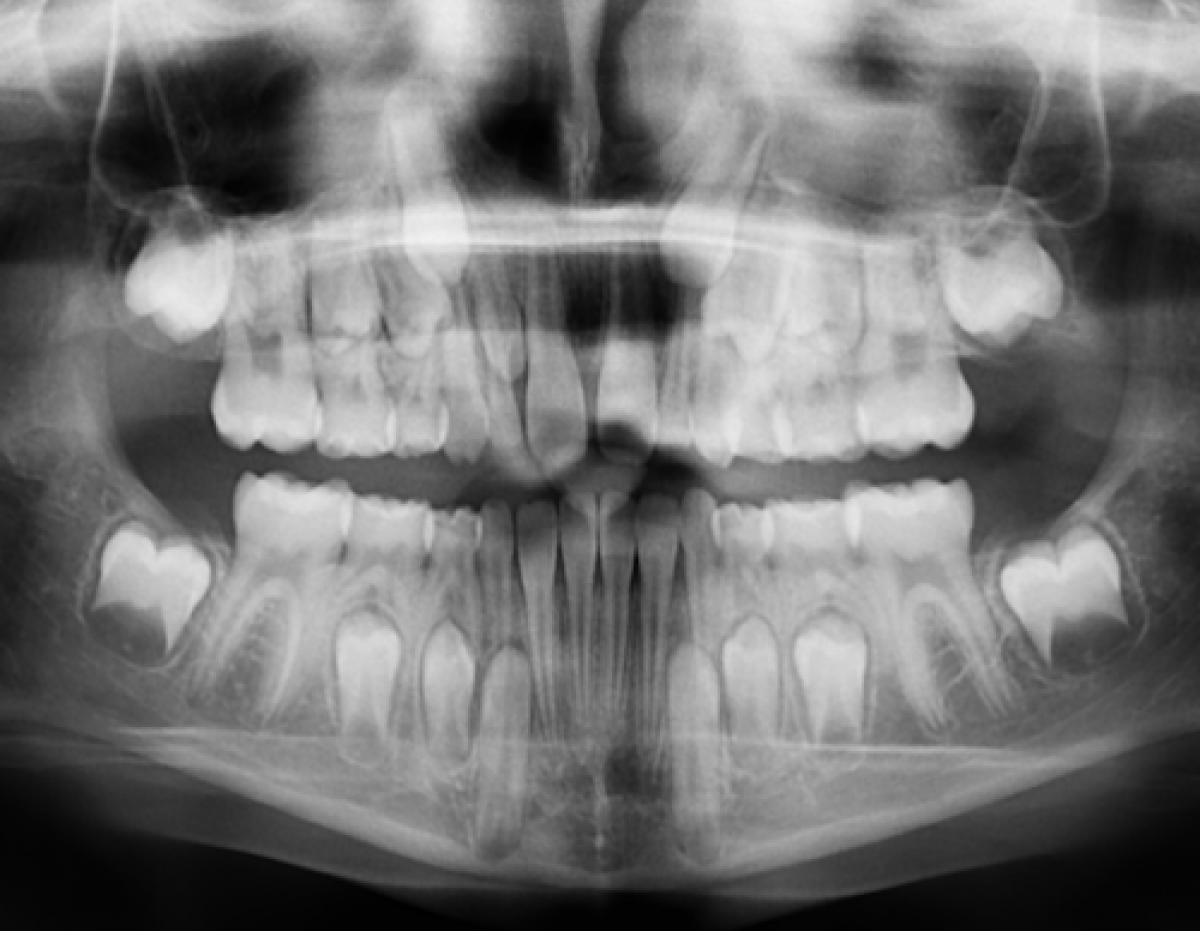

Detection of missing permanent incisors

The age at which incisor agenesis is initially clinically suspected is important, as this is when the dentist is likely to confirm this suspicion radiographically, or refer the patient to an orthodontist who will perform further investigations, potentially diagnose agenesis, and manage the case accordingly. The present study thus aims to determine the prevalence and distribution of clinically missing maxillary and mandibular permanent incisors, as well as the age at which they are detected, in a school-aged ethnically heterogeneous group of children.

In cases of suspicion of permanent incisor agenesis, the latest age when this was detected clinically with a good degree of certainty in this study was by 11.5 years. Before this age, late eruption cannot be excluded in a definitive manner, despite clinical diagnosis or at least suspicion being made significantly earlier on some occasions, even before the age of nine as seen in the current study.In fact, the results of the present study show that in roughly a quarter of children where permanent incisor agenesis was suspected between the age of 9 and 10, this turned out to be a false positive finding, with late incisor eruption occurring. Radiographic confirmation at the age of 11.5 may therefore be justified and the need to confirm the clinical suspicion of agenesis may outweigh the potential risks of irradiation during childhood.